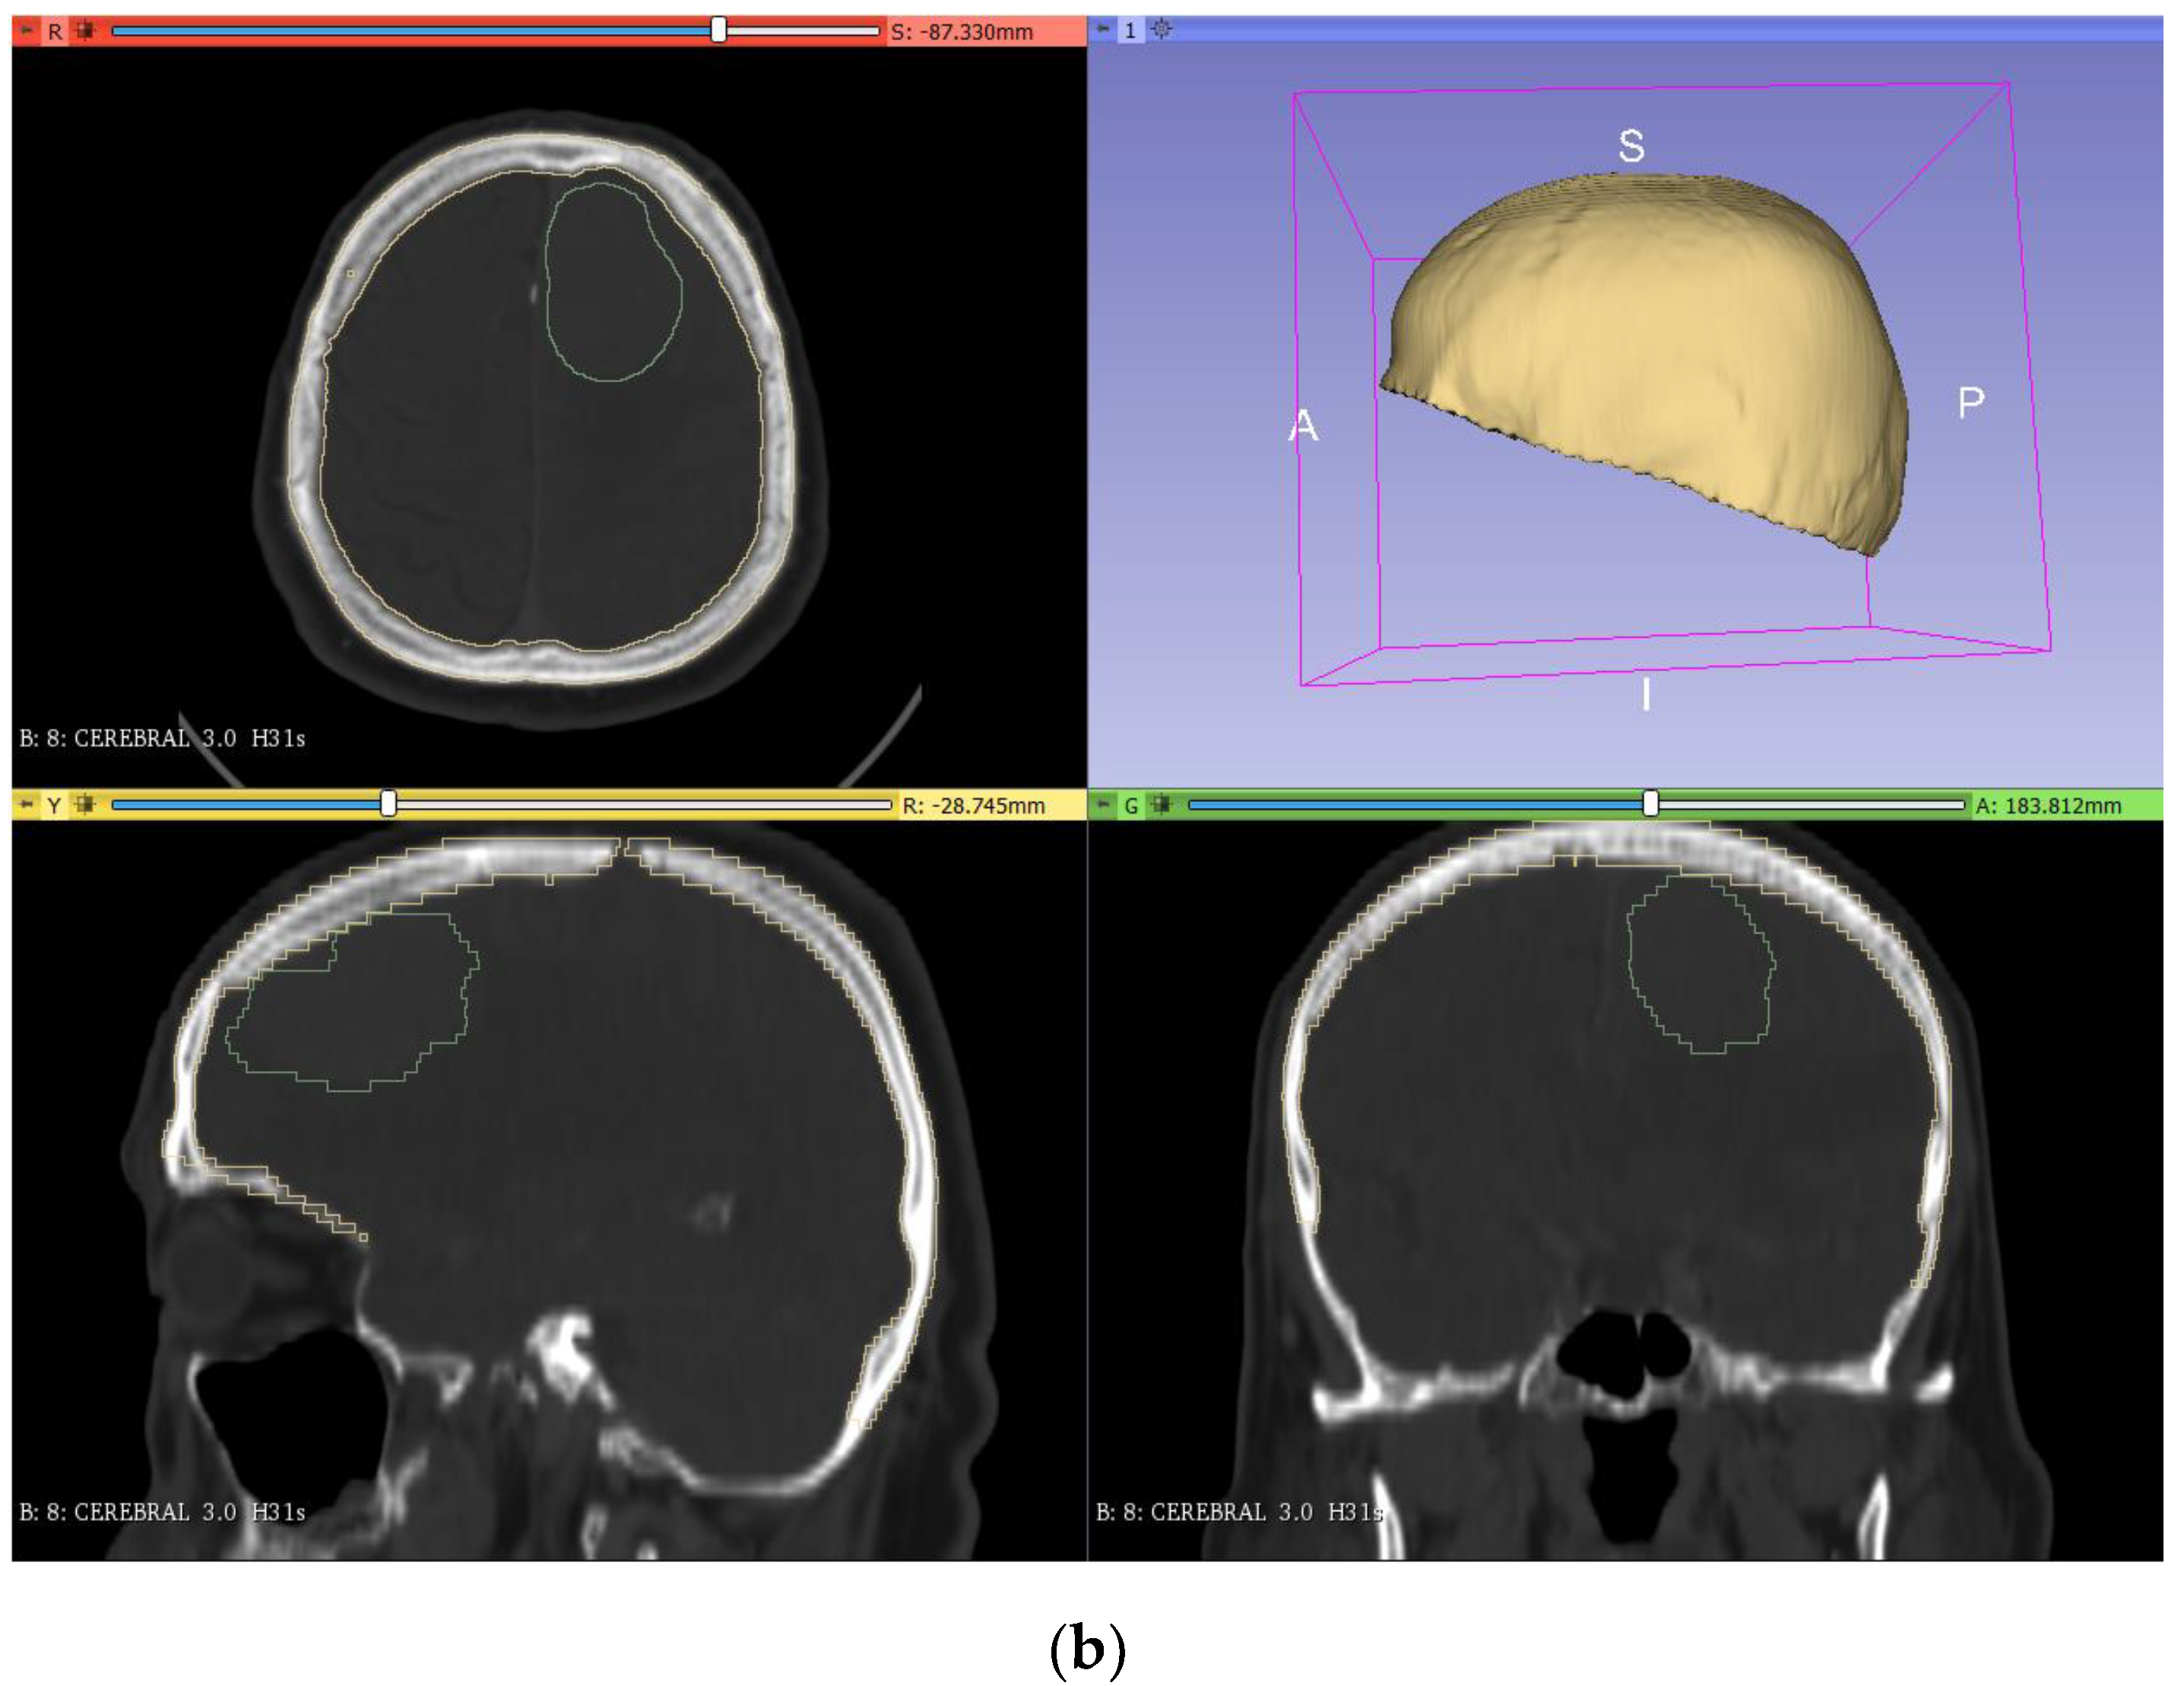

2.2.2. Tumor Mold

As mentioned above, the production of a tumor prototype requires a mold where the silicone mixture has to be poured to obtain the desired geometric model. To do this, the model was segmented (Figure 3a) using a similar approach to that applied for the bone segmentation. However, since the tumor is not easily differentiated from the brain, more manual work was needed. The first step was to apply the ‘threshold’ tool in the segment editor to try to select all the pixels corresponding to the tumor by adjusting the range of application. As the previous step was not accurate due to the color similarity between the brain and tumor, the ‘erase’ and ‘paint’ tools were used, layer by layer, to adjust the segmented area (‘erase’ to remove areas and ‘paint’ to add new areas to the segment). After this, a copy of the segmented model was made (‘logical operators’, ‘copy’ operation) with an added thickness of 10 mm (‘margin’ tool). Then, the original model was subtracted to the increased model (‘logical operators’ tool, ‘subtract’ operation), leaving a hollow segmented model as a mold (Figure 3b).

Figure 3.

Segmentation (a) and creation of the tumor mold (b) from the DICOM images in 3DSlicer.